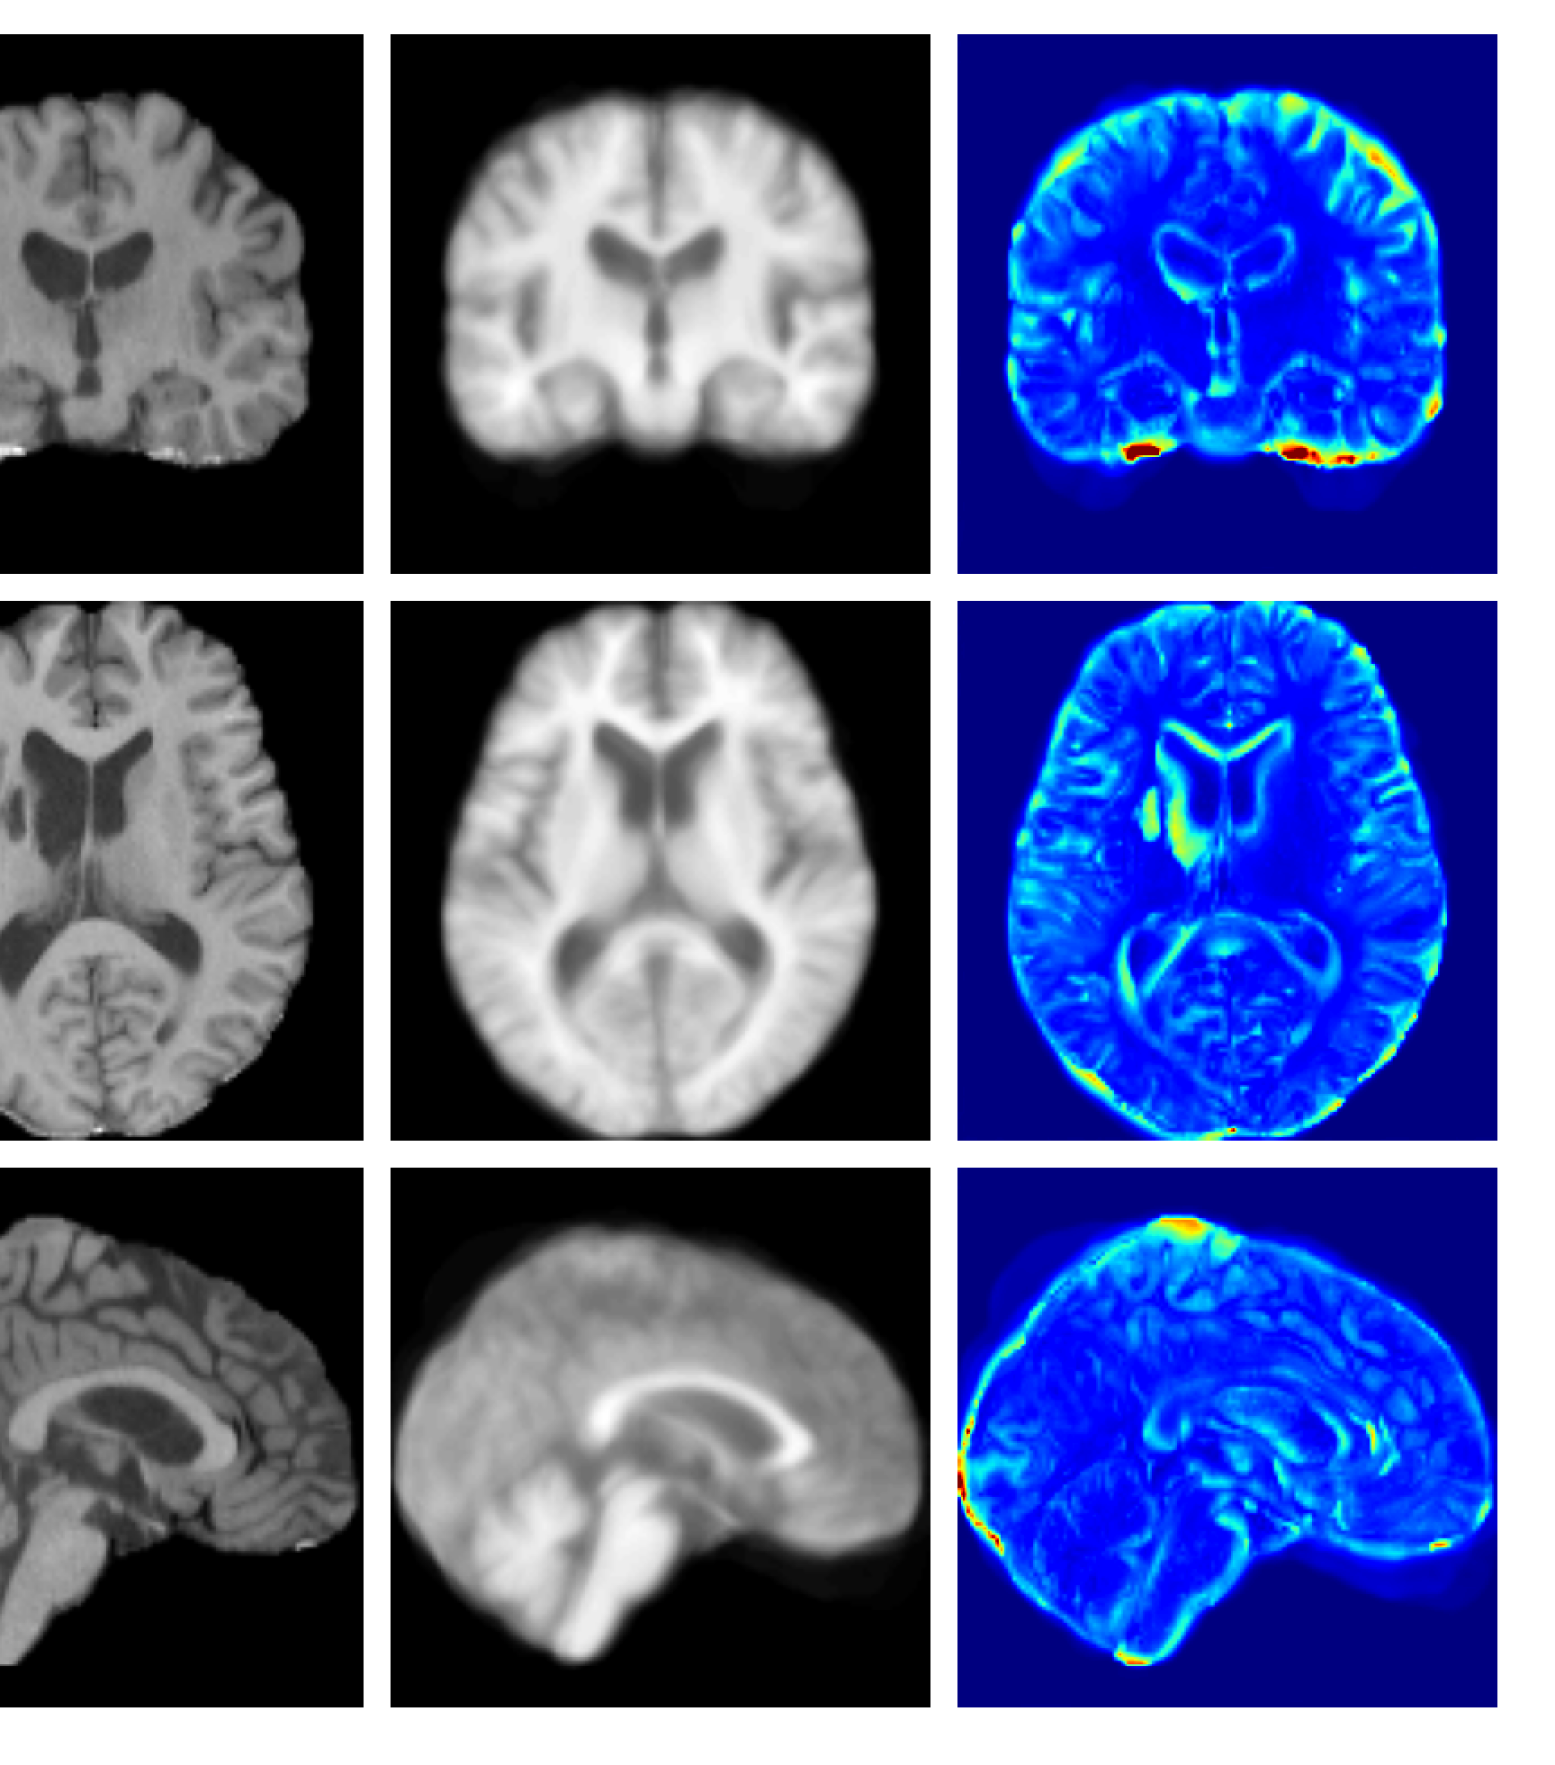

Figure 4: Example reconstructions and anomaly maps from a disease cohort sample in the UoTH dataset, shown for the top three models. The lesion is highlighted in red in the original image.

For the UoTH dataset, Table 2 shows that whilst CADD outperforms all other DDPM methods, it is outperformed by the VAE and cVAE models. Unlike the UKBB and ADNI datasets, the UoTH dataset contains noisy images with larger lesions and regions of pathology. Here, the CADD threshold, which limits the number of regions flagged as anomalous at each inpainting step, may be too stringent to fully inpaint extensive anomalies. It should be noted, however, that the improved disease detection performance of the VAE and cVAE models comes at the cost of accurate reconstruction of healthy tissue as illustrated in Table 1 and Figure 4. Such poor quality reconstructions would not be suitable for downstream tasks such as anomaly segmentation or image processing algorithms.

Figure 9: Enlarged example reconstructions and anomaly maps for a sample from the disease cohort of the XXXH dataset. The lesion region is indicated in the original image by the red box.